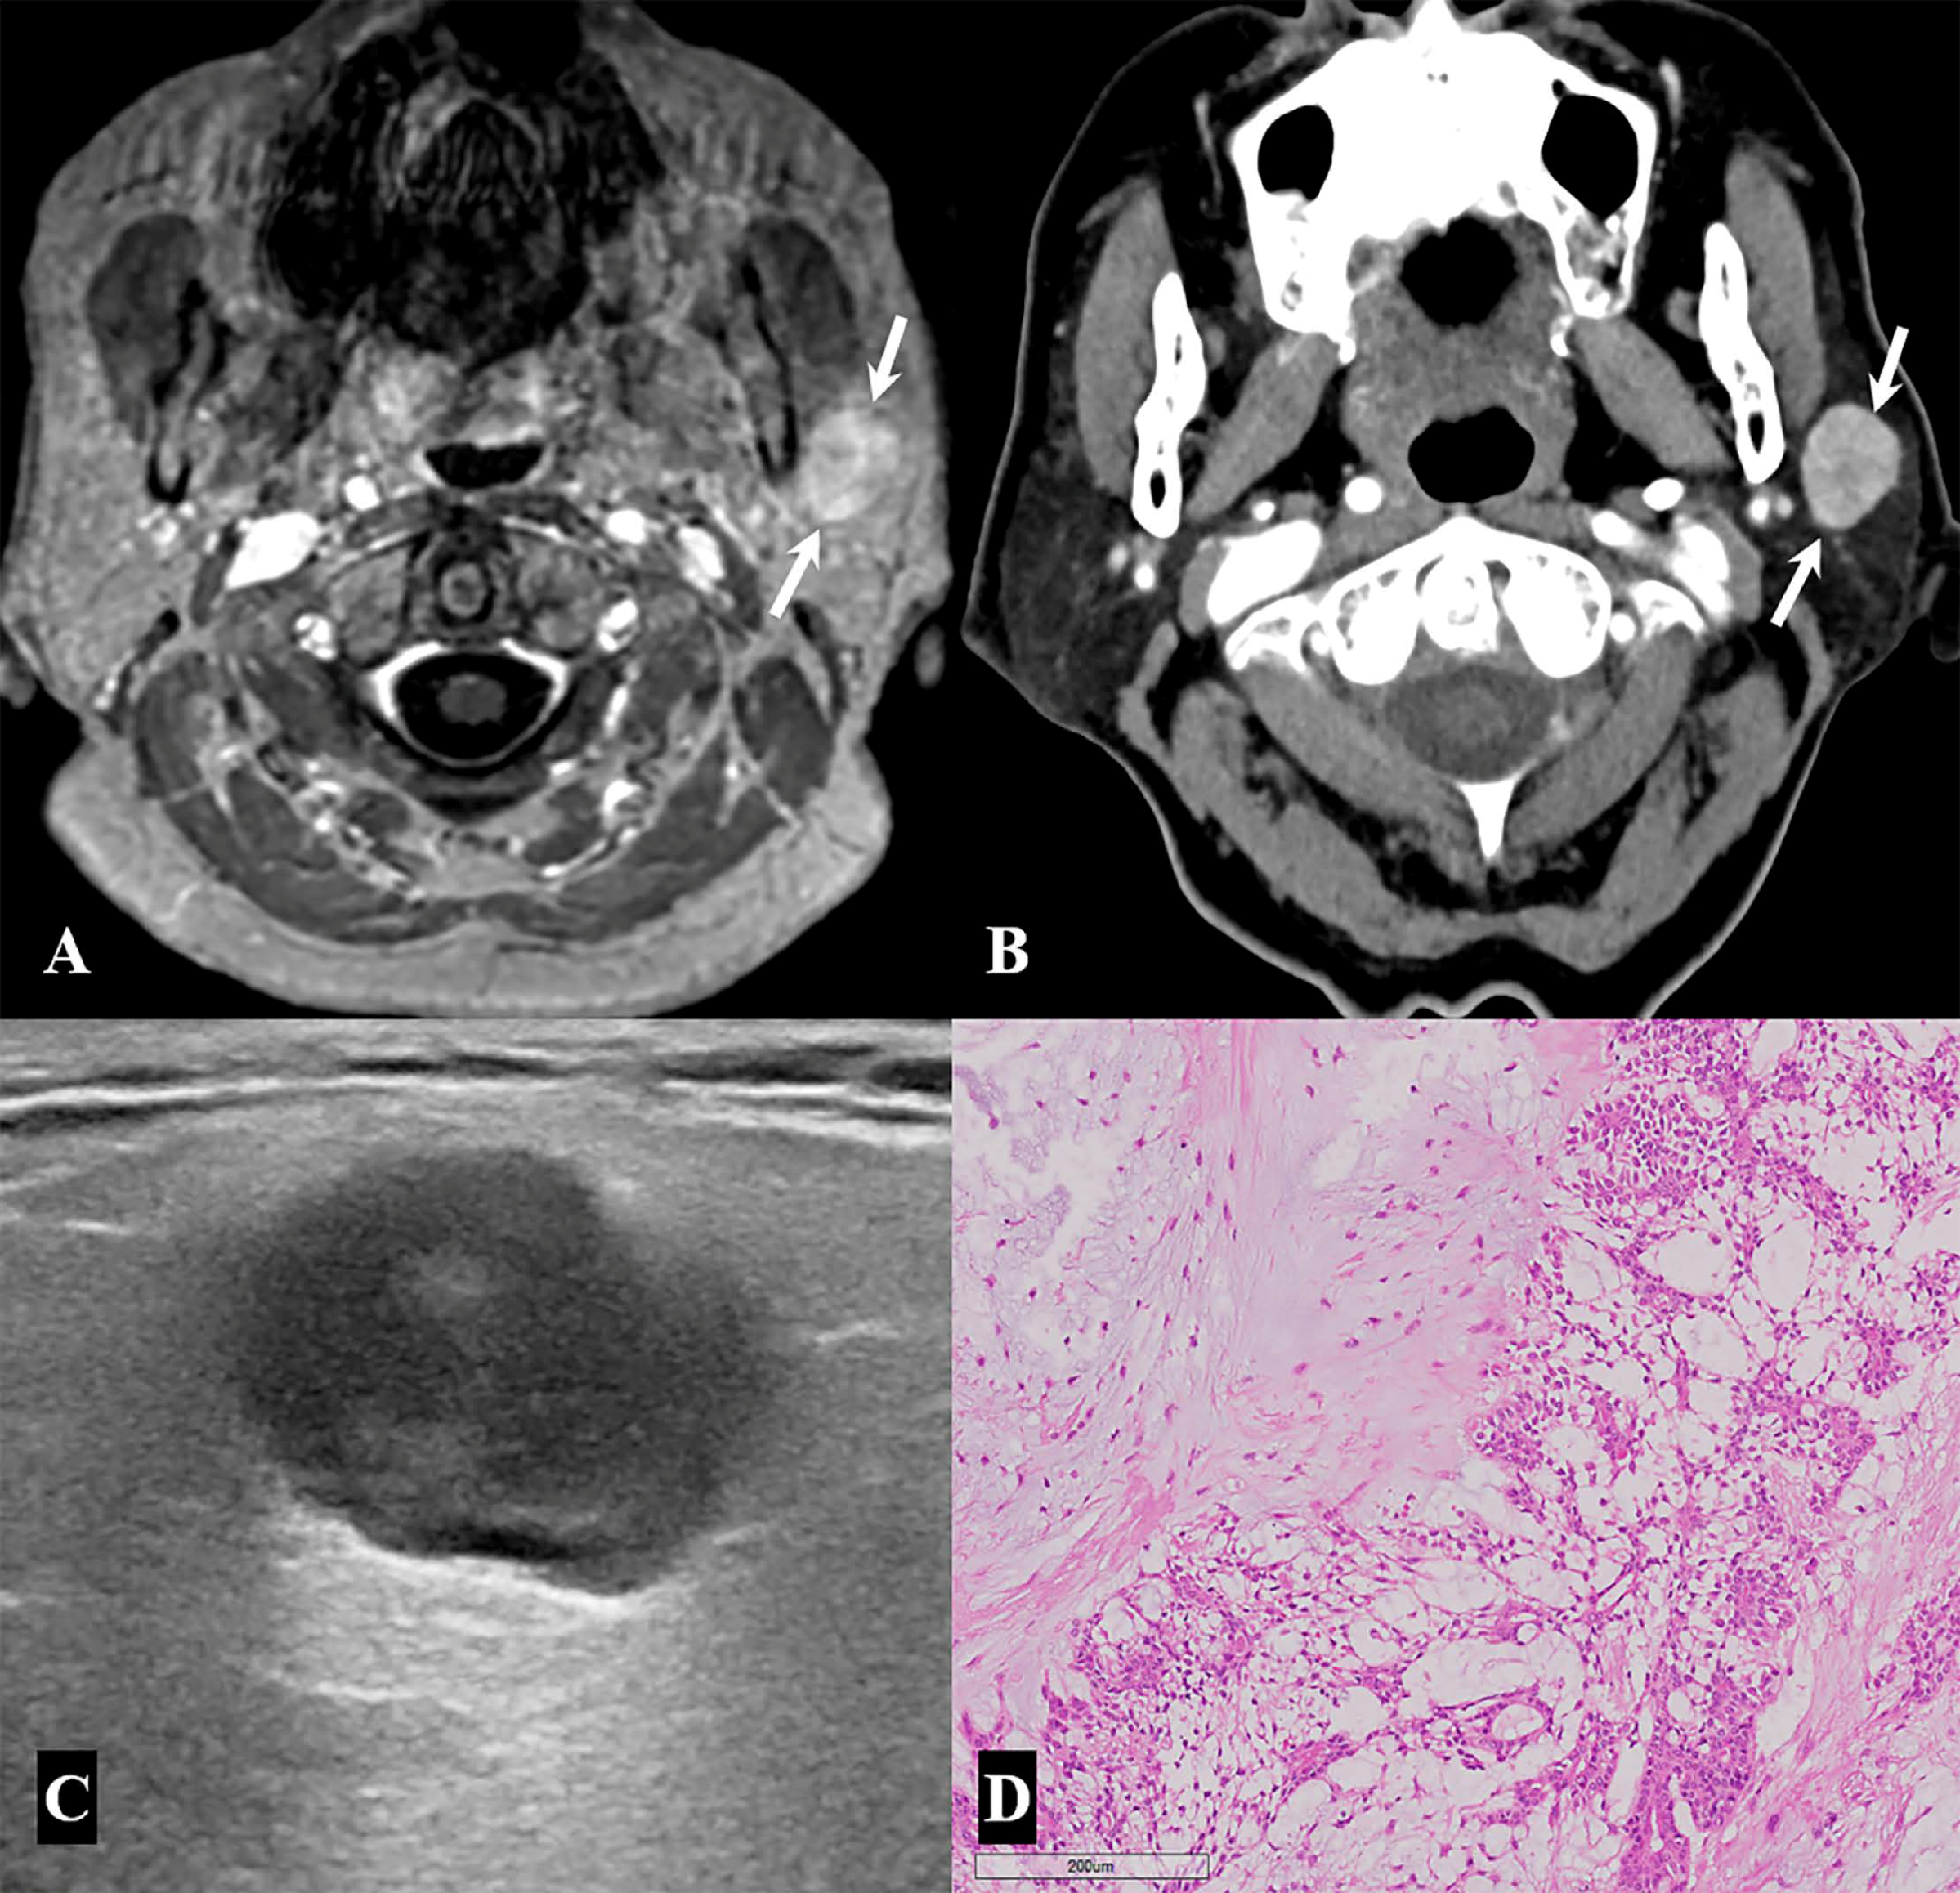

| Pleomorphic adenoma | 8/49 (16.3%) |